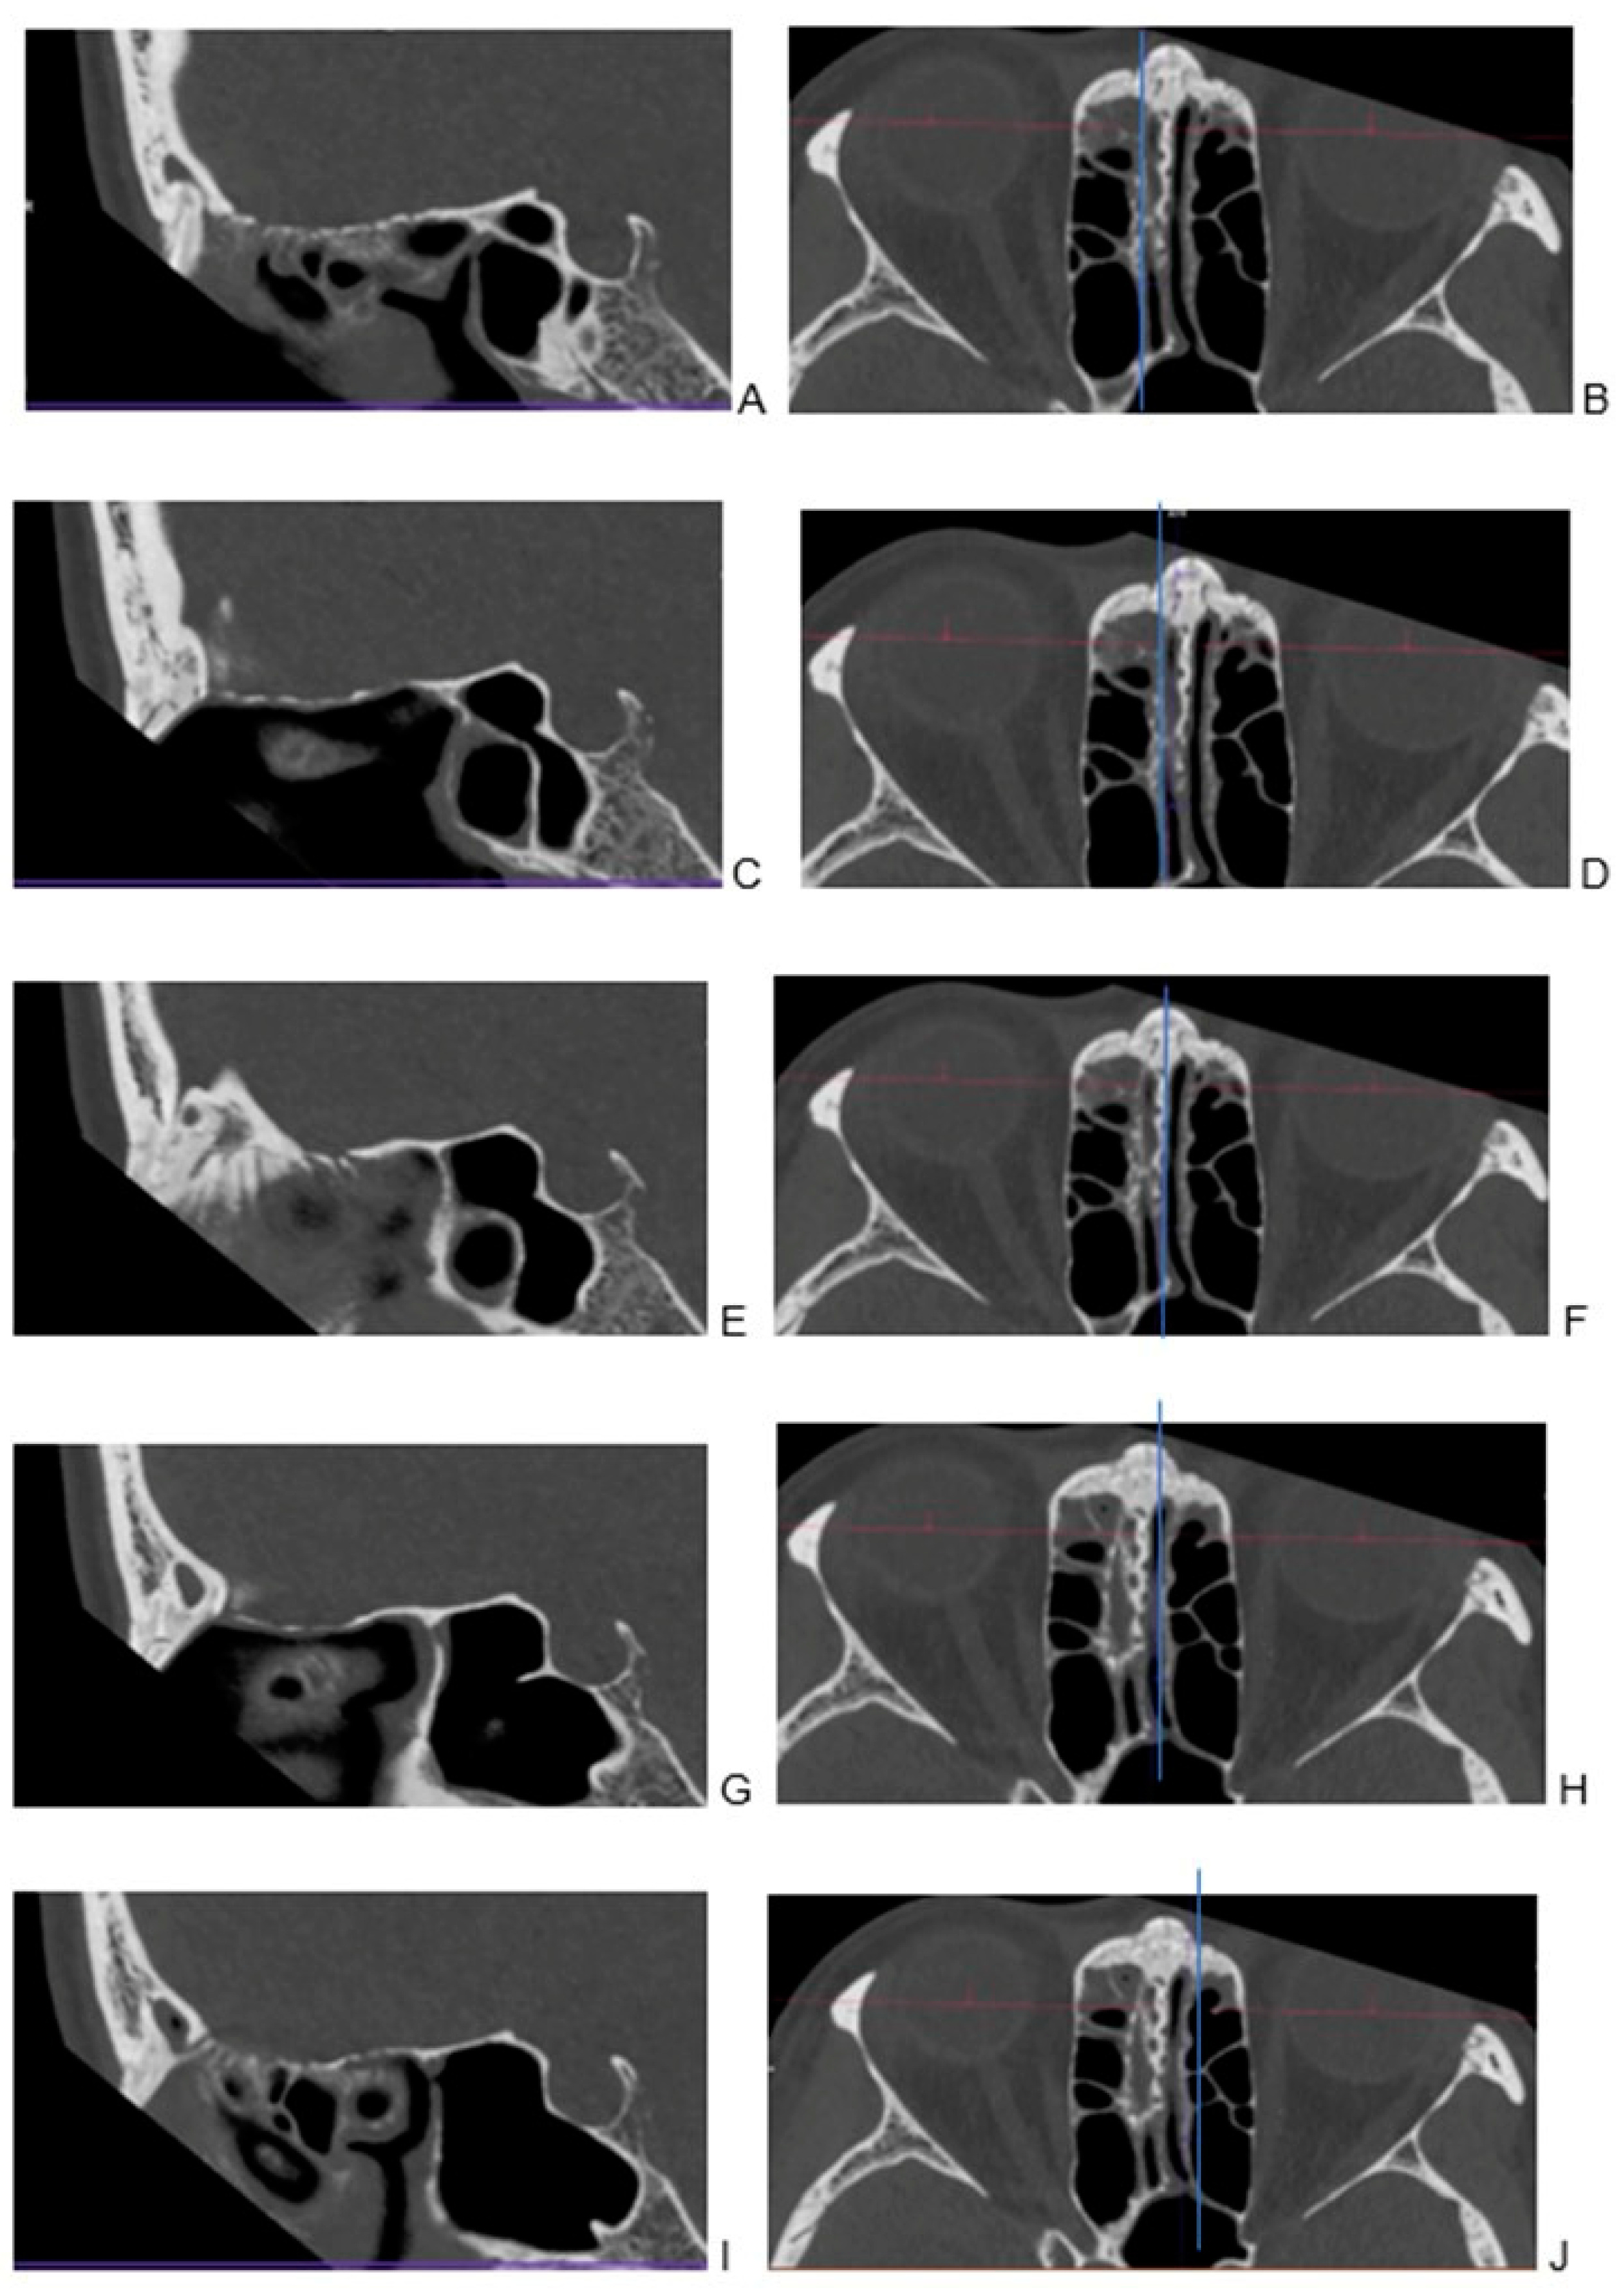

2.3. Image Preparation—Multiplanar Reconstructions